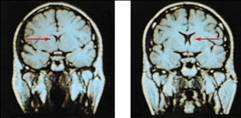

Clinical Observation

• Clinical observations have shed light on a number of brain disorders. Alterations in brain morphology due to neurological and psychiatric diseases are now being catalogued.